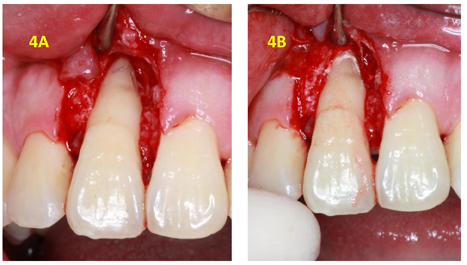

初诊4周后复查(2017年11月8日):检查:11舌侧暂封在,叩痛(-),Ⅰ度松动,唇侧牙周袋仍溢脓。处置:11拟翻瓣探查,翻瓣后11唇侧及近中见大量肉芽,刮治后11近中唇侧根中部见隐裂(图3),快机裂钻磨除隐裂(图4A),填MTA(图4B),填充骨粉后缝合(图5A),上牙周塞治剂(图5B)。

刘学军教授认为当牙根纵裂诊断确立后,应尽早拔牙或截除患根,以保存骨量进一步行种植、修复治疗。很多试图修复裂隙的措施都难以期待远期疗效,且增加骨缺损风险[1]。但因患者保留该牙意愿强烈,我们仍尝试进行治疗。该牙为上颌中切牙,无法像磨牙一样只截除患根保留剩余牙根。且其隐裂位置在根中部,无法行根尖手术截除根下段,否则剩余牙根太短预后不佳。受冠部隐裂磨除隐裂纹充填树脂的治疗方案启发,我们尝试快机磨除隐裂后充填生物相容性良好的MTA,植骨粉后缝合。该患者经过治疗后效果良好,骨质恢复,根管治疗术后3个月、半年、4年半复查均无异常。该案例通过根管治疗结合牙周翻瓣去除感染及裂隙备洞充填和植骨,成功地解决了根尖牙周联合性感染的治疗难题,为以后不完全根裂的治疗提供了案例支持。